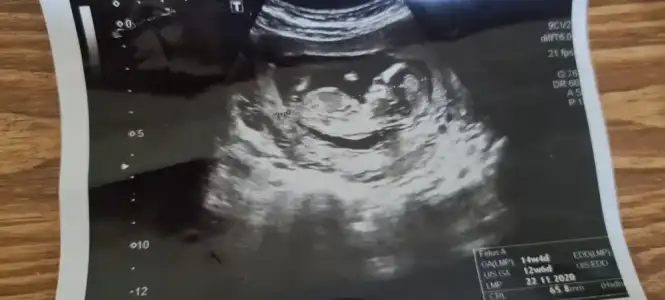

Merhaba Ikra meyra Ikra meyra şu çıkıntı kafamı karıştırdı, nub mudur sizce?🙈 Sanırım ilk resimde bebek ters dönmüş ama kafası düz bakıyor, yanılıyor muyum acaba...😬

Eklentiler

• 9747172E-C757-40B1-A39B-F2AE2EA9F4EE.webp

9747172E-C757-40B1-A39B-F2AE2EA9F4EE.webp

13,6 KB · Görüntüleme: 78

• 2A36C3B3-6077-4B26-BCF4-AF819C3A3B27.webp

2A36C3B3-6077-4B26-BCF4-AF819C3A3B27.webp

14,9 KB · Görüntüleme: 85